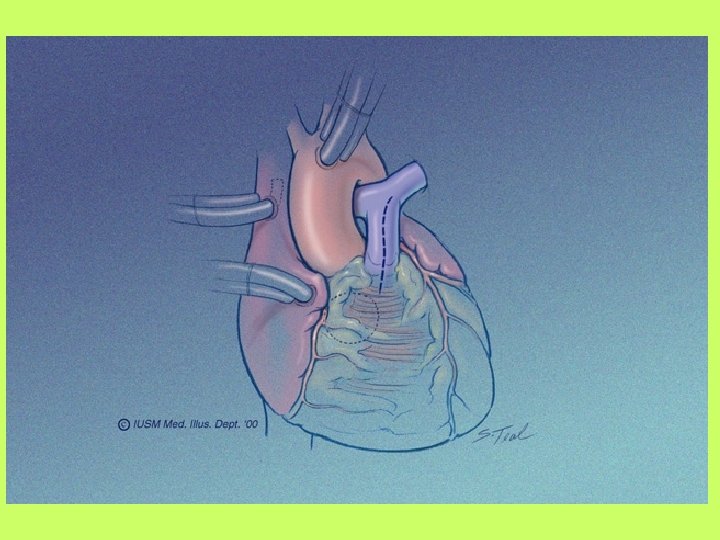

Cardiopulmonary by pass (CPB)